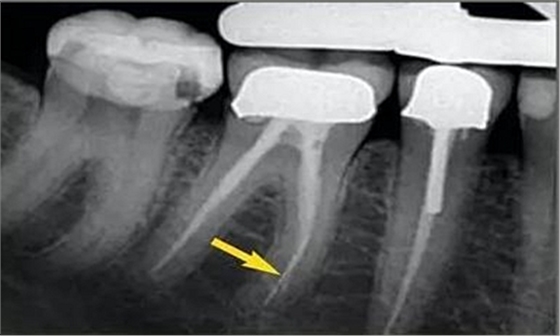

從近遠(yuǎn)中向的X光片可以看出,在根尖三分之一區(qū)域,根管形態(tài)較寬而且彎曲。通過彎曲之后,單只銼沿直線到達(dá)根尖,沒有清理的根管的唇側(cè)部分。遺漏的區(qū)域在近遠(yuǎn)中向的X光片中顯示得格外清晰。

唇面觀

近遠(yuǎn)中觀

預(yù)備后的根管橫切面